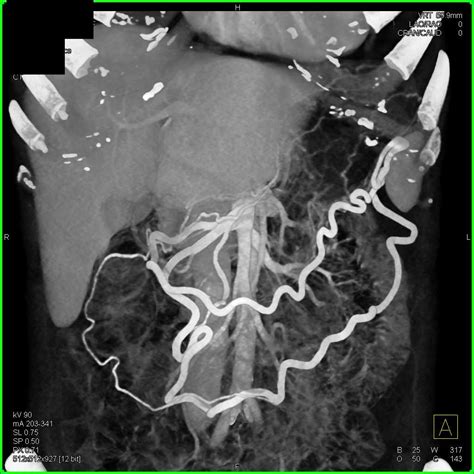

In addition to standard CT scans, advanced imaging techniques can provide even more detailed information about pancreatic adenocarcinoma. These techniques include:

• Magnetic Resonance Imaging (MRI): MRI uses magnetic fields and radio waves to create detailed images of the body. It can provide more information about soft tissues and is often used in conjunction with CT scans.

• Positron Emission Tomography (PET) Scan: A PET scan uses a radioactive tracer to highlight areas of high metabolic activity, which can indicate the presence of cancer cells. It is often combined with a CT scan (PET/CT) to provide both functional and structural information.

These advanced imaging techniques can complement the information provided by a Pancreatic Adenocarcinoma CT Scan, helping to create a comprehensive picture of the cancer's extent and characteristics.